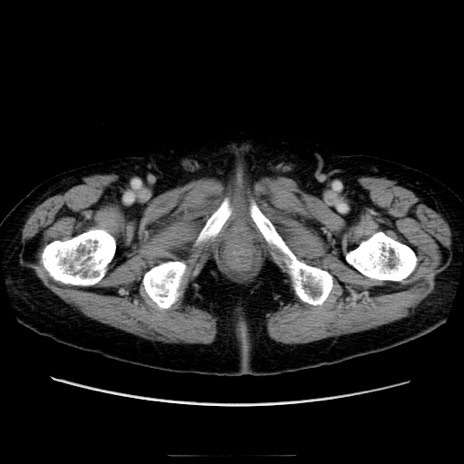

症例21(横断像)

【症例】70歳代男性

【主訴】腹痛

【現病歴】肝硬変・肝細胞癌にてかかりつけの方。約9時間前に食後より腹痛出現。症状が徐々に増悪し、嘔吐出現したため来院。

【既往歴】肝硬変、肝細胞癌(RFA、TACE後)

【身体所見】意識清明、表情苦悶様、BT 36℃、BP 129/78mmHg、P 88bpm、SpO2 97%(RA)、右上腹部から心窩部にかけて圧痛あり、反跳痛なし、筋性防御あり。

【データ】WBC 5800、CRP 0.16